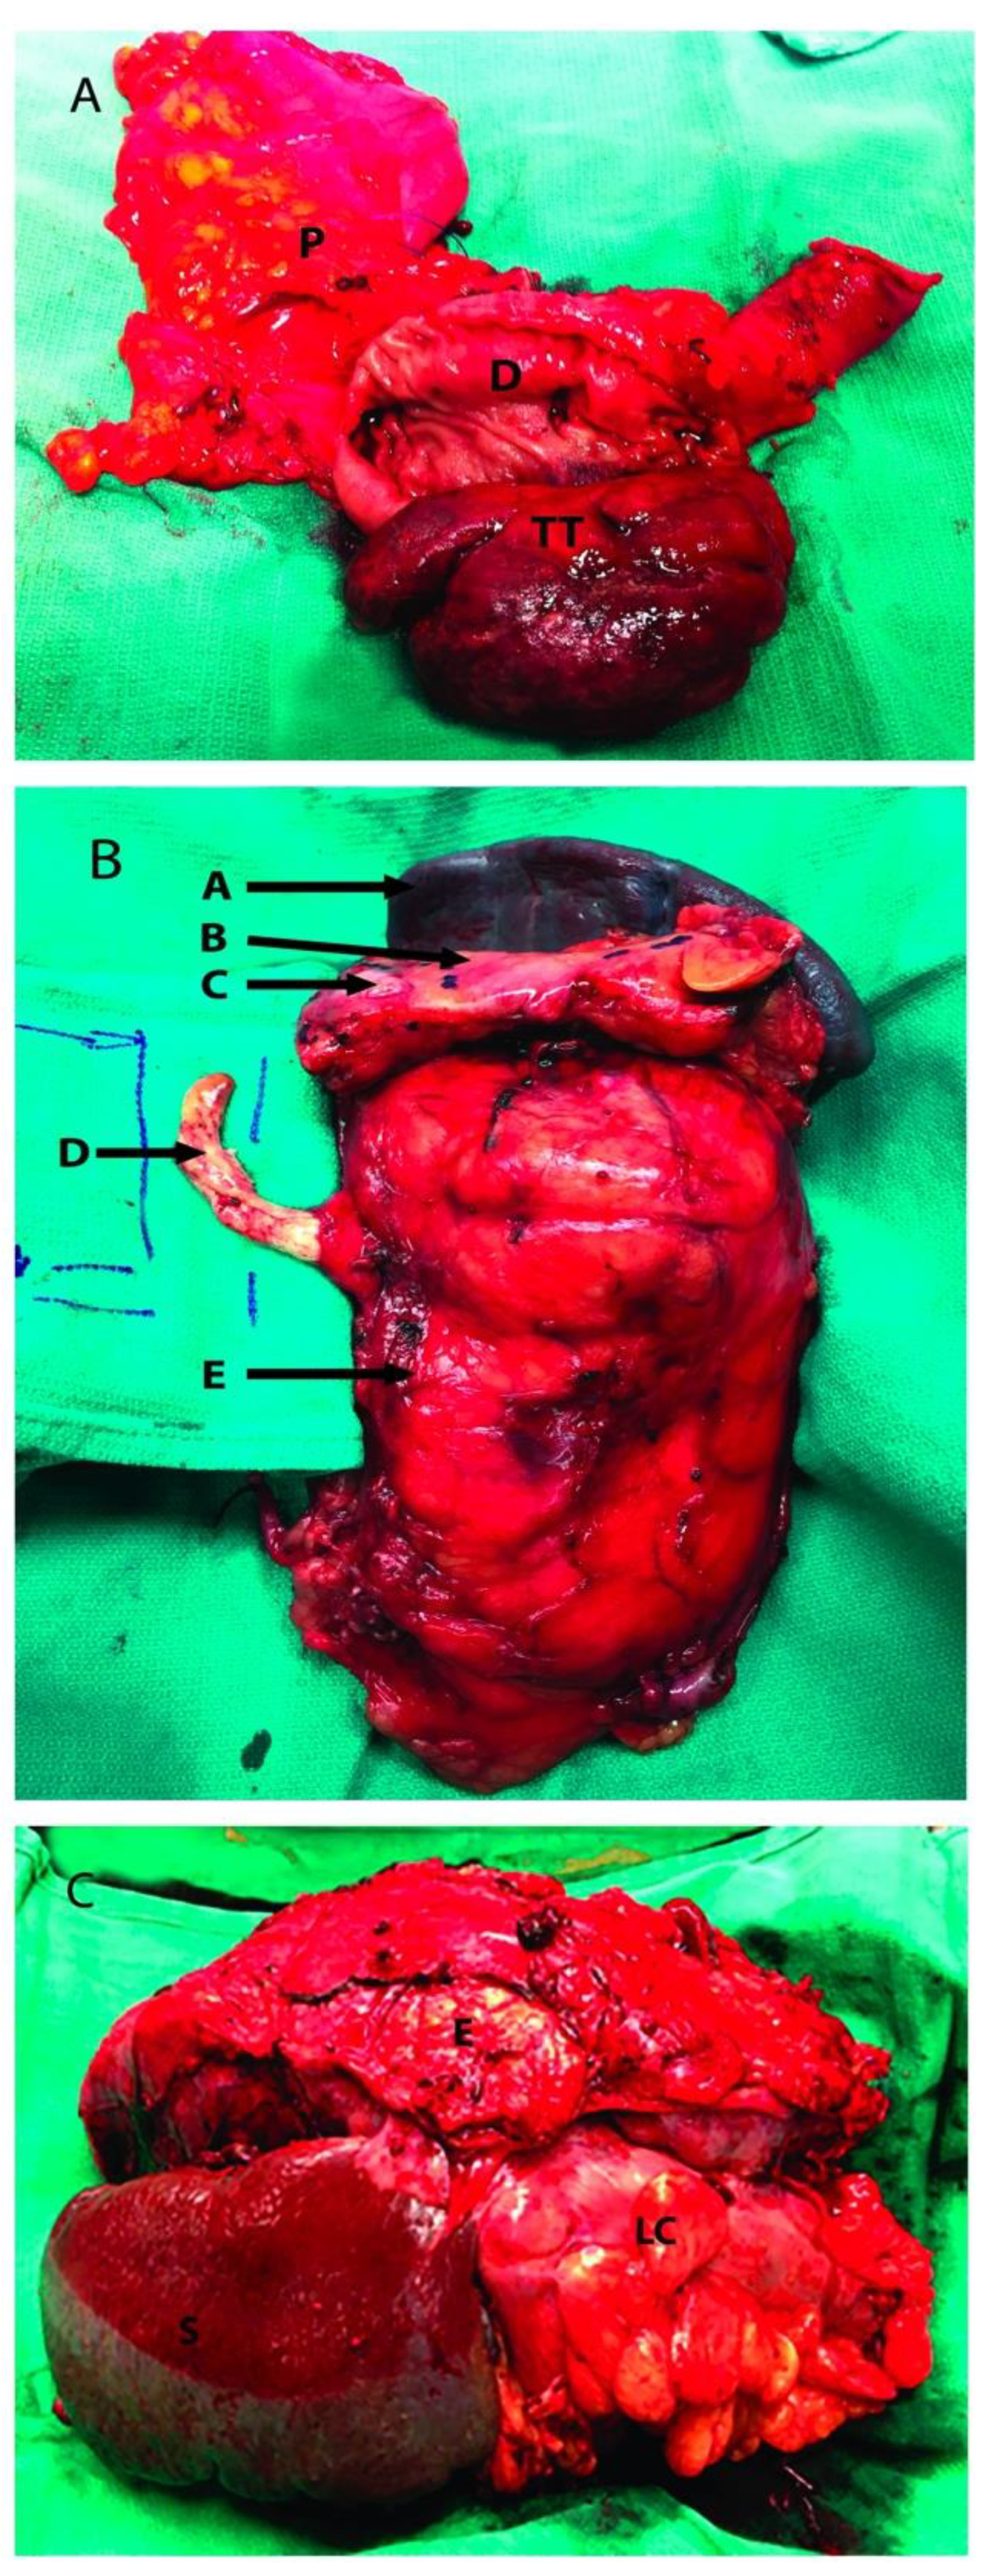

Partially occluding (level I or II) thrombi were managed by tangential cavectomy and primary closure. Completely occluding (level II and III) tumor thrombi required circumferential cavectomy (i.e., segment located between the caval bifurcation and the inferior border of the major hepatic veins entrance) without vascular reconstruction. The level IIIb tumor thrombus was “milked” and controlled below the major hepatic veins before the cavectomy was attempted (Figure 2) [18].

Figure 2.

Renal tumor involving adjacent organs. (A): Head of the pancreas resected along with a portion of duodenum; (B): Left radical nephrectomy specimen with resection of IVC tumor thrombus, pancreas and spleen; (C): Left kidney tumor resected with adjacent organs, the distal pancreas was not visualized. P: Head of pancreas; D: 2nd portion of duodenum; TT: Tumor thrombus inside the second portion of the duodenum; A: Spleen; B: Pancreas; C: Pancreatic metastatic mass; D: Tumor Thrombus going inside the inferior vena cava; E: Kidney Tumor; S: Spleen; LC: Left Colon.